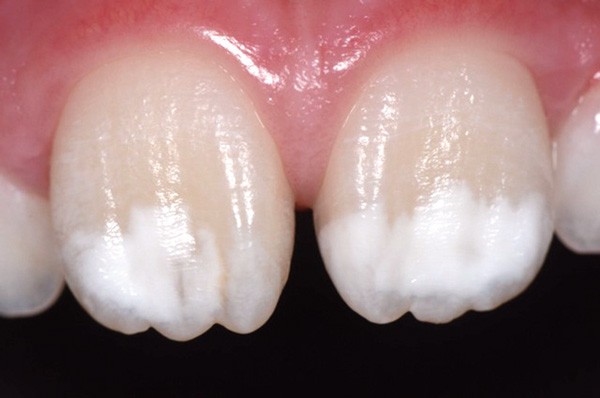

Traitement ultra-conservateur des taches de l’émail : bilan avec 5 ans de recul

Les auteurs de cette conférence nous proposent un algorithme pour résoudre le problème des taches blanches de l’émail. Ces techniques sont désormais utilisées avec succès depuis 10 ans. Tout d’abord il convient souvent de réaliser un éclaircissement préalable : celui-ci diminue le contraste entre la tache et le reste de la dent. Ensuite, avant de poser le champ opératoire, il faut choisir la teinte du composite qui sera nécessaire à la fin du traitement. Un sablage/fraisage des taches les plus profondes est alors réalisé, en fonction de la profondeur de la tache. Vient alors l’infiltration ou masquage optique, qui fonctionne sur les taches blanches : on passe une solution d’acide chlorhydrique, puis une solution d’hypochlorite de sodium, et si la tache est devenue blanche alors il est possible de passer à l’infiltration par la résine. Enfin, s’il subsiste une concavité visible, un composite viendra la combler. Le polissage clôt alors le protocole(fig. 11 et 12).